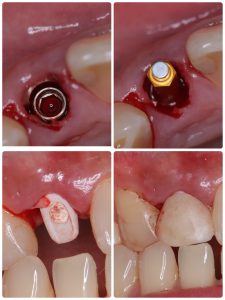

昼からは前歯抜歯即時、ソケットシールド、即時荷重まで 切開無し